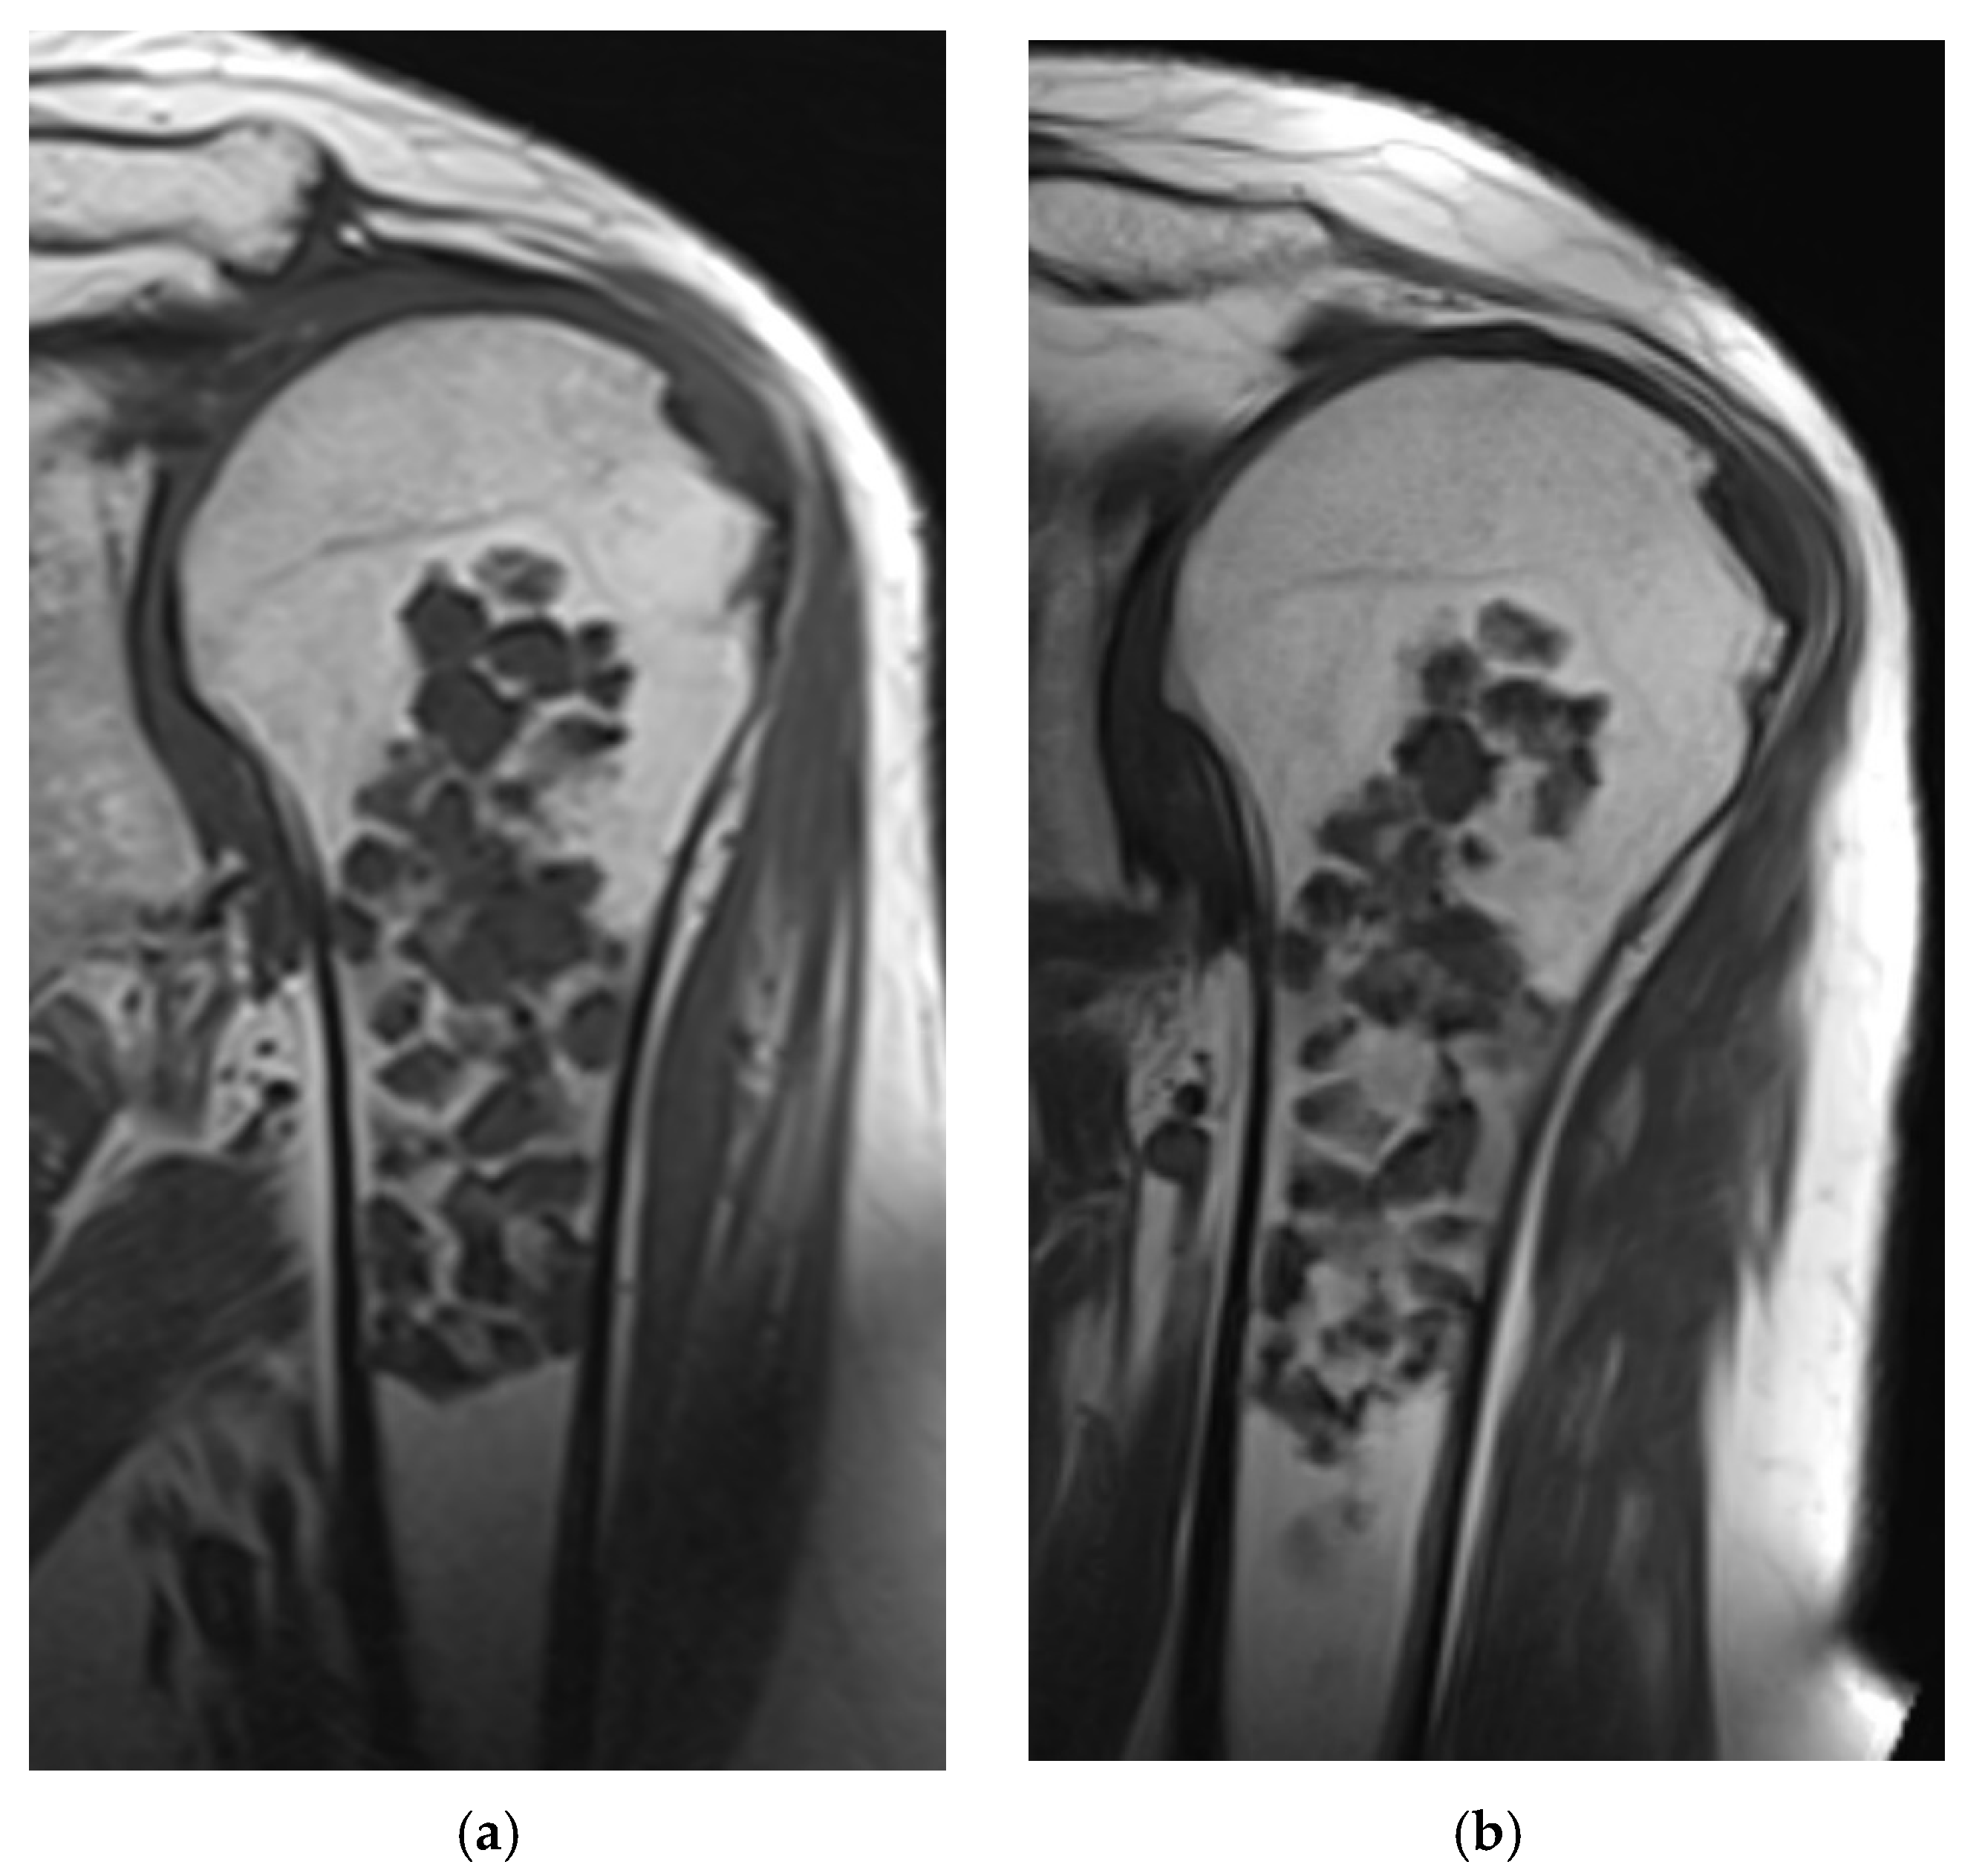

3.2. MRI Analysis